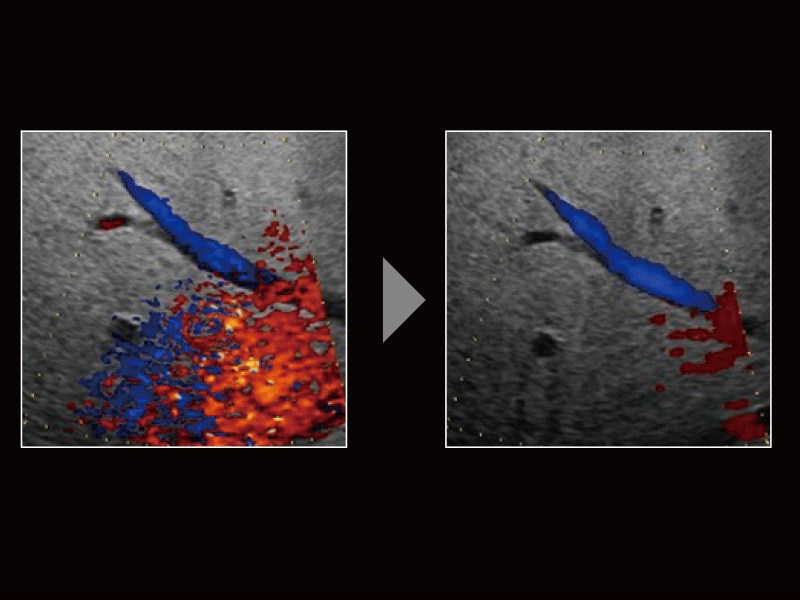

Detective Flow Imaging (DFI), which is a micro vascular flow imaging technology, has supported noise processing technology “Wall Motion Reduction PLUS” so that body motion noises are suppressed selectively, and images of high sensitivity and visibility can be realized. “Wall Motion Reduction PLUS” judges the scattering of detected signal intensity to perform noise reduction according to the body motion amount of each region.

DFI

Judge the scattering of signal intensity to reduce noise

-Realize higher sensitivity by filter processing improvement and signal velocity scattering judgement-

Flow sensitivity is improved by shifting the wall filter to the low velocity side. With the filter processing changed, body motion noises are reduced effectively by detecting the signal velocity scattering in multiple-times receiving and judging them.